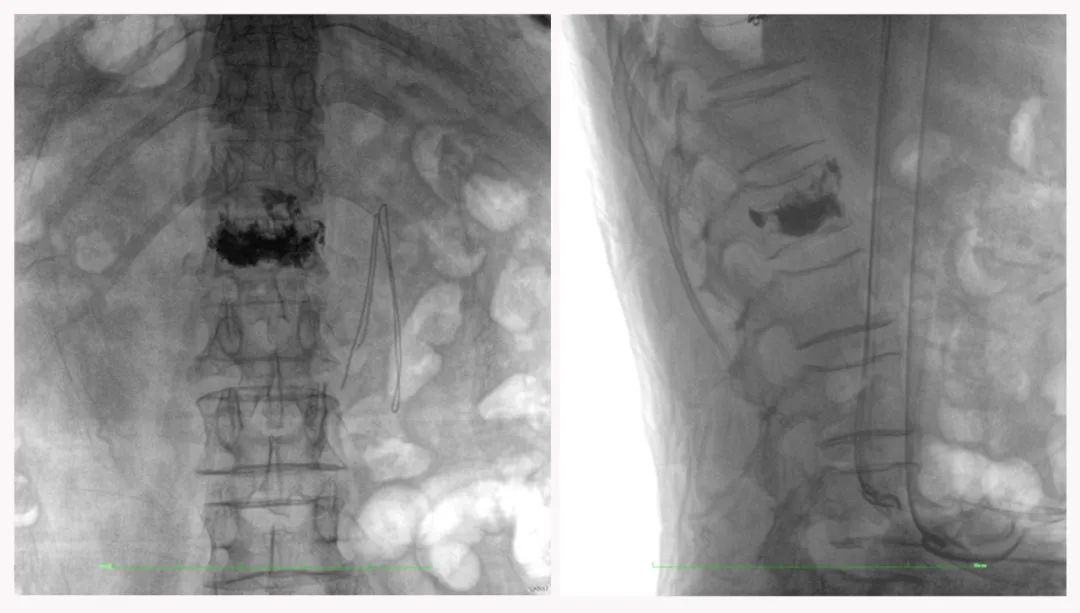

二維正側位影像

三維“類CT”影像

病例1:右側股骨遠端骨骺骨病(13歲)

二維影像看不到病灶點

三維切面影像可以看出病灶點